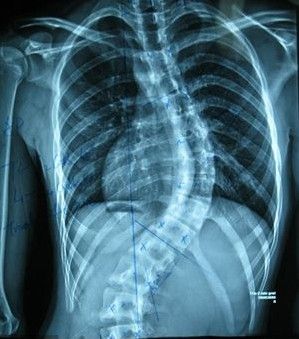

强直性脊柱炎是很常见的一类疾病,它的发生严重危害着广大朋友们的健康生活,那么在生活中具体引起强直性脊柱炎的原因有什么呢,那么下面就为您介绍一下强直性脊柱炎的病因有哪些吧。成都强直医院排名怎么样?

第一、内分泌原因。强直性脊柱炎男性发病率明显高于女性,尤其是男性在14-17岁为本病发病的高峰年龄,此年龄正是男性的青春发育期。因此,考虑此病发病是否与男性内分泌激素有关。总之,此病至今对强直性脊柱炎的病因尚无明确结论。这四种病因的集合即可发病。

第二、家族遗传原因。强直性脊柱炎的家族遗传性早已受到医学家的重视,医生在对强直性脊柱炎家族的普查时发现,该病患者家属中的平均患病率为4%,而全国人口平均患病率仅为0.1%,两者之间发病率竟相差40倍,说明家族遗传性确与强直性脊柱炎的发病有关。

第三、风寒湿致病原因。本病属于风湿类疾病的范畴,所以使人很容易想到强直性脊柱炎的病因和风寒潮湿的关系,本病也确实在高寒和潮湿地区发病率较高,是本病的一种诱发因素。